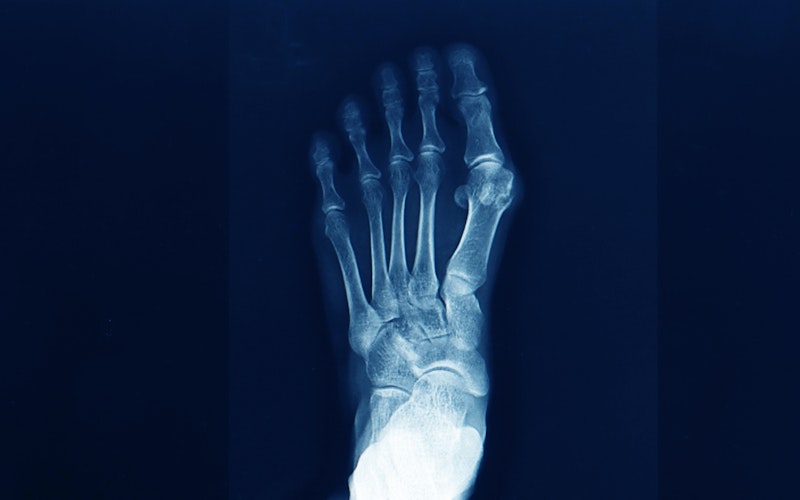

If you're dealing with foot pain, bunions are easy to spot. Unlike other foot conditions such as corns, calluses, or ingrown toenails, bunions are predominantly found along your big toe.

View on GoogleWhat Causes Bunions?

Have you recently hurt your toe, tendons, or any other part of your foot? Or do you live with arthritis? It's possible that either one can impact how you walk or can change your foot structure, creating the perfect conditions for bunions to form.